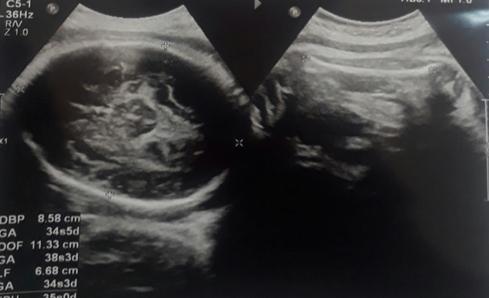

Hipertensión pulmonar severa y embarazo. reporte de un caso clínico

Severe pulmonary hypertension and pregnancy. report of a clinical case

Choquecallata, Walter Andrés Terceros,..........................................................................................68-73 Carta al Editor